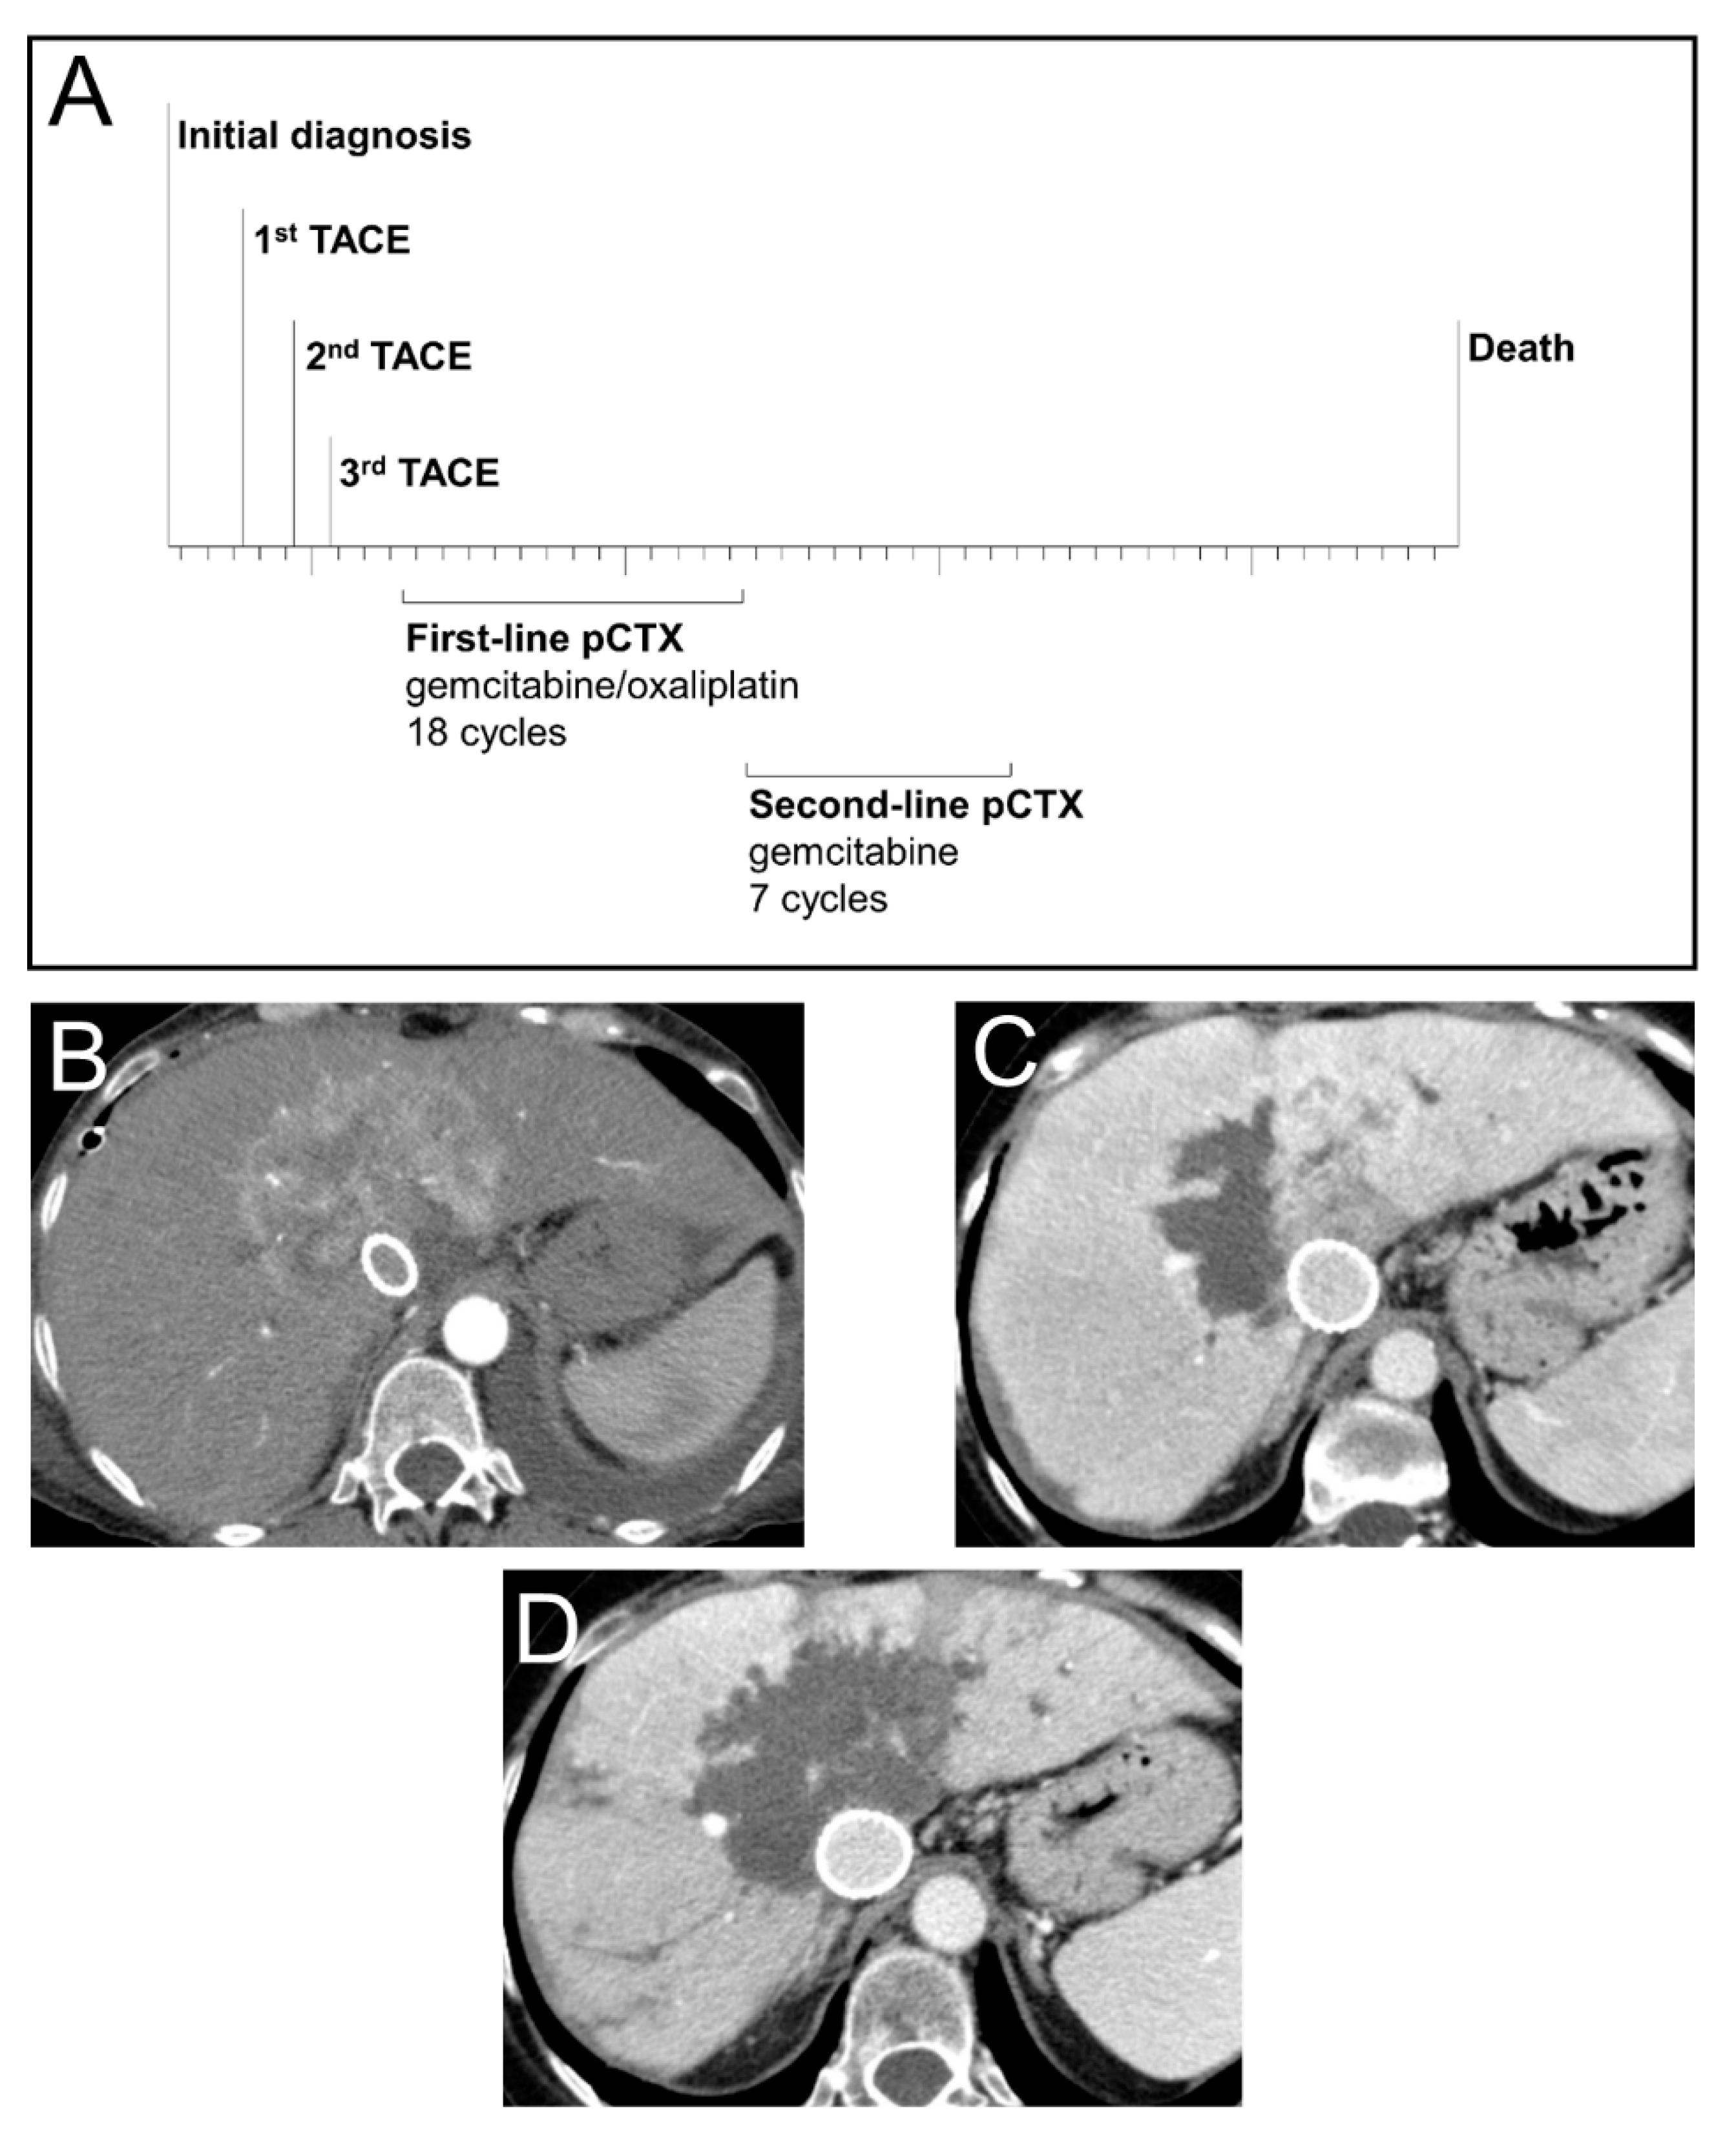

3.5. Case Study